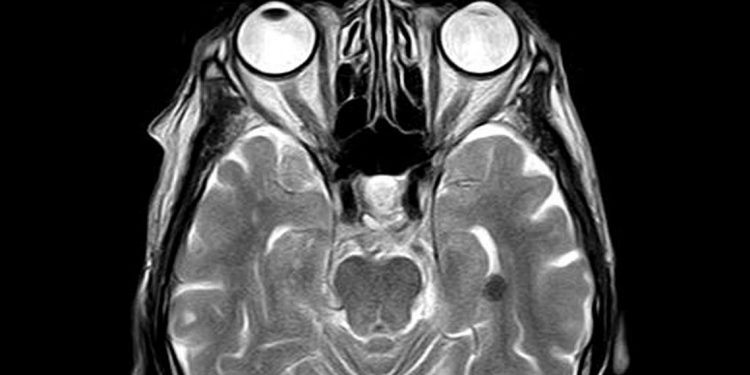

Pemindaian otak Magnetic Resonance Imaging (MRI) mengungkapkan bahwa orang dengan infeksi COVID-19 yang parah memiliki lebih banyak ‘pembuluh tali’ yang tidak dapat dilalui darah, menurut penelitian berjudul ‘The SARS-CoV-2 main protease Mpro cause microvascular brain pathology yang membelah NEMO di sel endotel otak.

Pembuluh tali mewakili jaringan sisa setelah sel mati di pembuluh darah, sehingga darah tidak mungkin melewatinya.